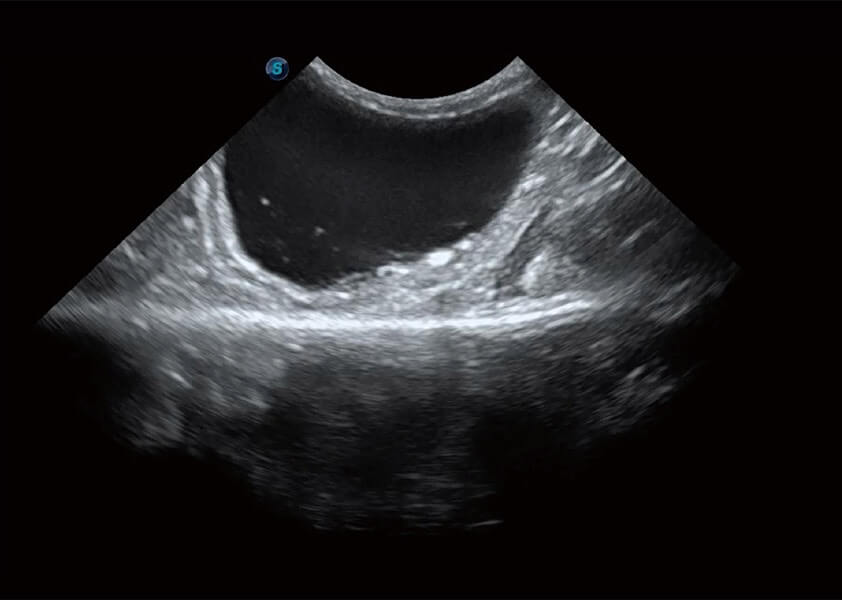

ProPet 60 作为一款高端台式动物超声设备,为动物医生的日常诊断提供了一系列贴合动物临床需求、解决临床实际问题的高级成像功能。凭借全系列高清探头,满足医生对腹部、心脏、生殖、浅表、肌骨等成像的所有需求,切实帮助您提升检查效率,提高诊断信心。

兽用彩色多普勒超声诊断系统

动物是人类最亲密的朋友和最值得信赖的伙伴。环球UG官网也一直致力于探索动物专用的超声影像解决方案。 全新推出的ProPet系列,是环球UG官网在动物超声影像智能化、专业化、精准化的一次跨越式革新。动物不能用言语来表述自己的不适,通过超声影像,ProPet系列搭建了动物医生与不同物种沟通的“桥梁”,为动物医生注入了“治愈之力”。